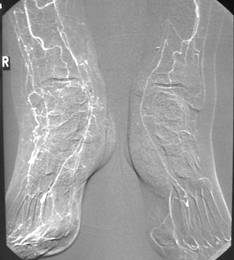

Die moderne Gefäßchirurgie hat sich inzwischen zu einer spezialisierten Fachdisziplin entwickelt, die häufig durch Wiederherstellung einer ausreichenden Durchblutung (Bypass, Aufdehnung,...) zur Erhaltung von amputationsbedrohten Beinen beiträgt. Hierfür ist allerdings eine exzellente Diagnostik der vorherrschenden Gefäßsituation bis zu den Füßen erforderlich. Eine unzureichende Darstellung der Durchblutungssituation kann zu Fehleinschätzungen mit nachfolgender Amputation führen. Zusätzlich spielt die Erfahrung des Gefäßchirurgen in Rekonstruktionen bis zum Fuß eine entscheidende Rolle (spezialisiertes Zentrum). In diesen Kliniken können nicht vermutete gefäßchirurgische Möglichkeiten zum "rettenden Strohhalm“ für den Patienten und auch deren Angehörigen werden.

Gefäßdarstellung beider Füße für gößeres Bild bitte klicken